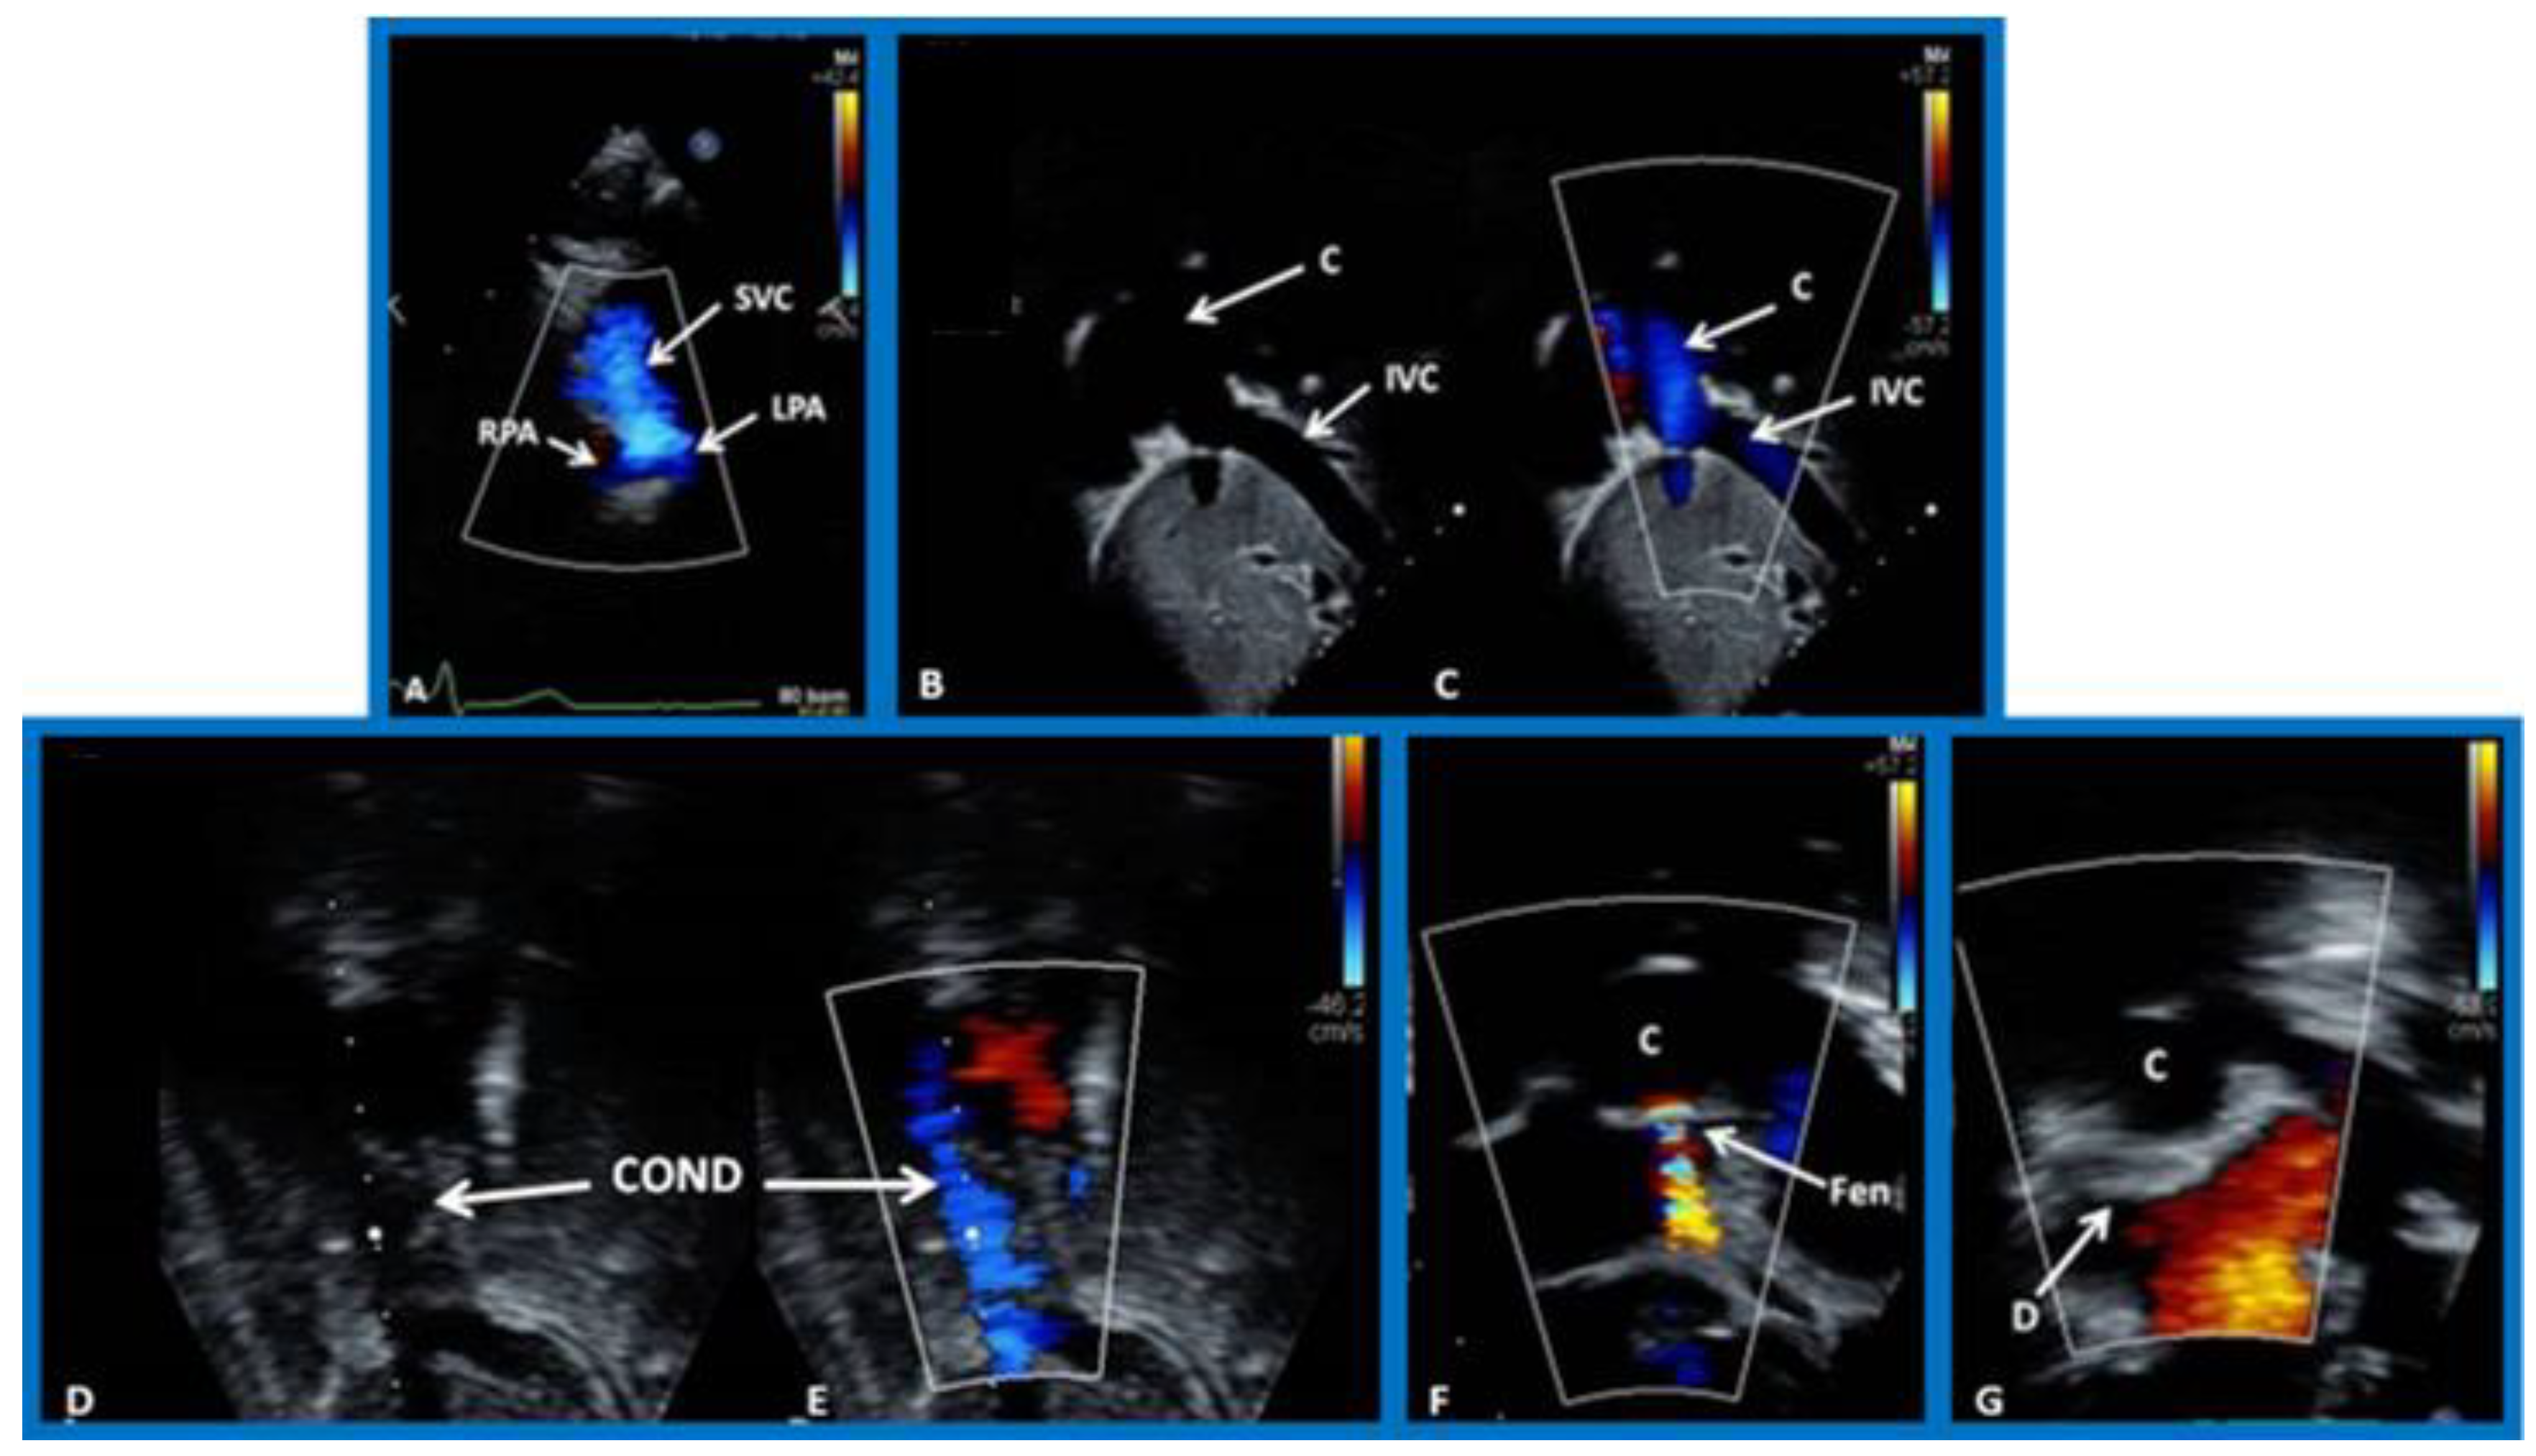

8. Echocardiogram

9. Cardiac Catheterization with Angiography, Magnetic Resonance Imaging (MRI) and Computed Tomography (CT)

10.4. Follow-Up after Palliative and Corrective Surgery